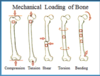

Bones work as

Levers and Shock Absorbers

Bones have ?

Intrinsic strength to resist

Designed for function( name 3)

Intrinsic strength to resist external forces or stresses

Shock absorption

Distribution of external stresses